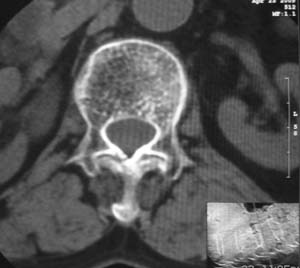

患者,女,72岁,胸背部疼痛3月余,无明显外伤史。曾应用局部封闭、非甾体类止痛药治疗效果不明显,近来疼痛缓解频感背困,平卧缓解,近日行ct检查发现胸12椎体病变,烦请同道发表意见,诊断什么?有何治疗经验!谢谢!!!

标绘图示:第十二胸椎级第一腰椎椎体楔形改变。ct扫描示:第十二胸椎椎体骨质结构紊乱,并可见一囊状低密度影,边缘可见硬化,椎体皮质完整。

考虑:第十二胸椎陈旧性骨折、许莫氏结节。